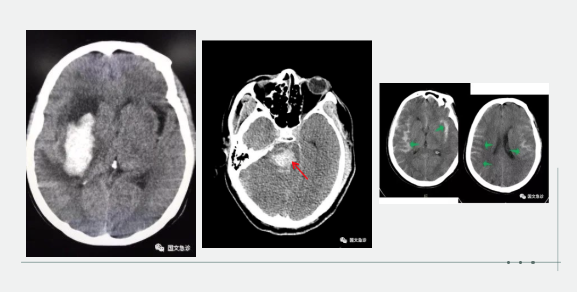

突發(fā)意識(shí)不清兩小時(shí)入院。據(jù)家屬描述“發(fā)現(xiàn)的時(shí)候老爺子躺在地上叫了好幾聲也沒有反應(yīng),上去推了推也沒動(dòng)靜趕忙就打120了。根據(jù)該家屬的描述,緊急為患者進(jìn)行查體:該患者意識(shí)成昏迷狀態(tài),查體不合作,雙側(cè)瞳孔等大等圓,呼吸間斷 血壓237/115mmhg。內(nèi)科醫(yī)生進(jìn)一步向家屬了解患者既往血壓情況,該家屬表示:“血壓一直都很高,降壓藥也不按時(shí)吃就難受的時(shí)候吃一片”。進(jìn)一步考慮患者腦內(nèi)出血,立即行頭部CT。為患者打開急診綠色通道“遵循檢查或繳費(fèi)的原則”。CT結(jié)果顯示患者左側(cè)大腦半球出血、小腦出血、腦室積血。醫(yī)生立即向家屬交代病情,該家屬哽咽著說(shuō):“你說(shuō)這早上剛還一起吃團(tuán)圓飯呢,一轉(zhuǎn)身的工夫,老爺子就倒地不起了。醫(yī)生您說(shuō)啊,好好的一個(gè)人怎么就腦出血了?以前除了血壓高一點(diǎn)癥狀都沒有呀!”

突發(fā)意識(shí)不清,1小時(shí)入院。該妻子滿眼淚水地向醫(yī)生訴說(shuō):“我們剛吃完飯,他說(shuō)困了睡一會(huì)兒,這怎么突然就叫不醒了呢?醫(yī)生您快看看,這是咋了呀?”“李先生平時(shí)身體怎么樣?”“我家老李平時(shí)身體可好了,你別看他長(zhǎng)得胖,一年感冒的次數(shù)都少。對(duì)了,就是血壓有點(diǎn)高。”根據(jù)家屬描述,立即為患者查體:該患者呈深度昏迷狀態(tài),雙側(cè)瞳孔不等大 左側(cè)3.5mm、右側(cè)5.0mm,血壓250/190,雙側(cè)病理征陽(yáng)性。初步考慮患者腦內(nèi)出血,急行頭部CT檢查。結(jié)果示:右側(cè)小腦及腦干不規(guī)則高密度灶破入腦室,三腦室及四腦室內(nèi)見高密度灶?;颊卟∏槲V蒯t(yī)生立即為患者辦理入院,急忙送往ICU(重癥監(jiān)護(hù)室)進(jìn)行進(jìn)一步治療。